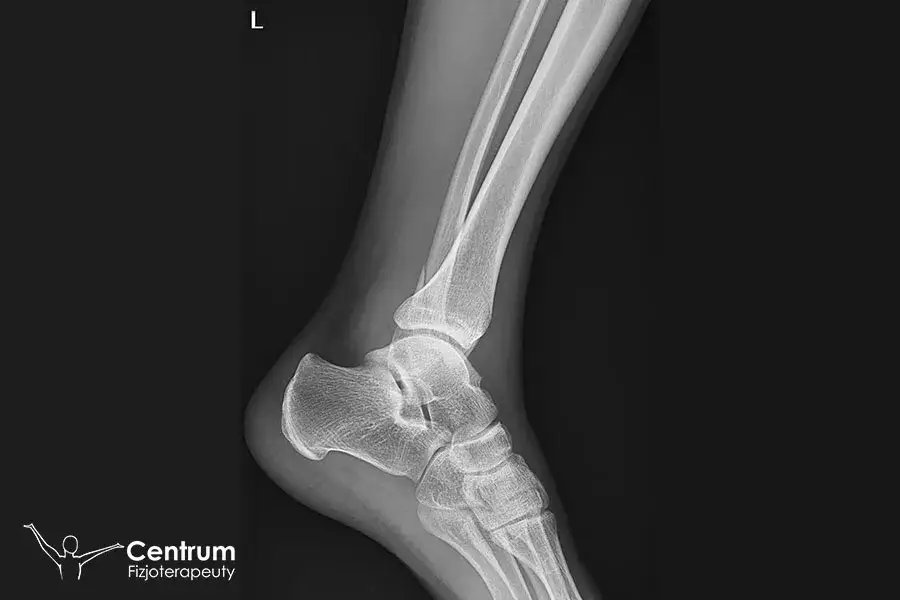

Złamanie kostki to poważny uraz, który wymaga odpowiedniego leczenia i rehabilitacji. Ten artykuł dostarczy Ci kompleksowych informacji na temat tego, jak długo trwa powrót do pełnej sprawności, jakie czynniki wpływają na ten proces oraz czego możesz spodziewać się na poszczególnych etapach rehabilitacji, abyś mógł świadomie i aktywnie uczestniczyć w drodze do zdrowia.

Rehabilitacja po złamaniu kostki: jak długo trwa i od czego zależy powrót do sprawności?